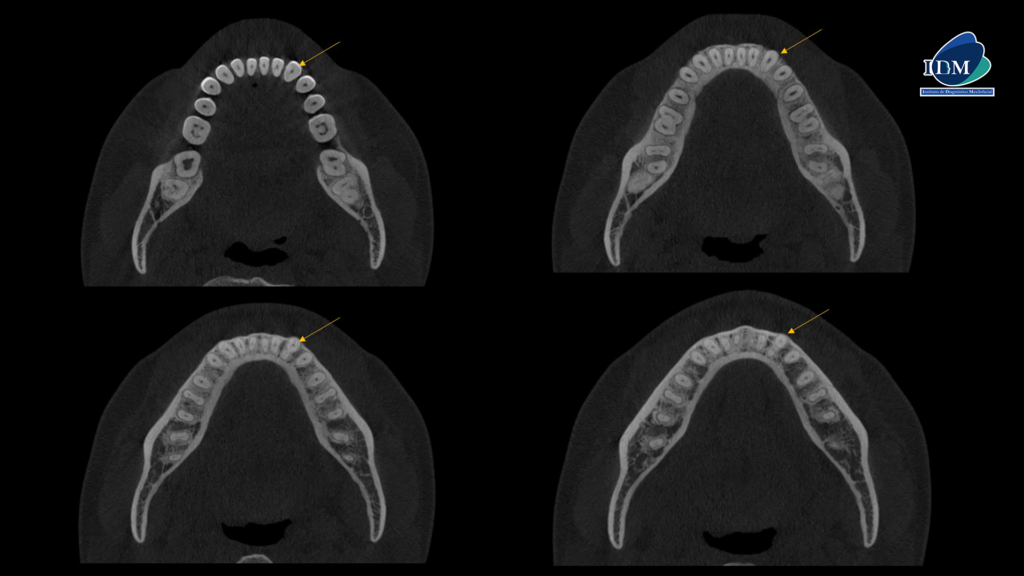

A la evaluación de la tomografía volumétrica (cone beam) en los cortes axiales (Figura 2) y transaxiales (Figura 3) se observa la bifurcación del conducto radicular a nivel del tercio medio radicular.

CORTES AXIALES